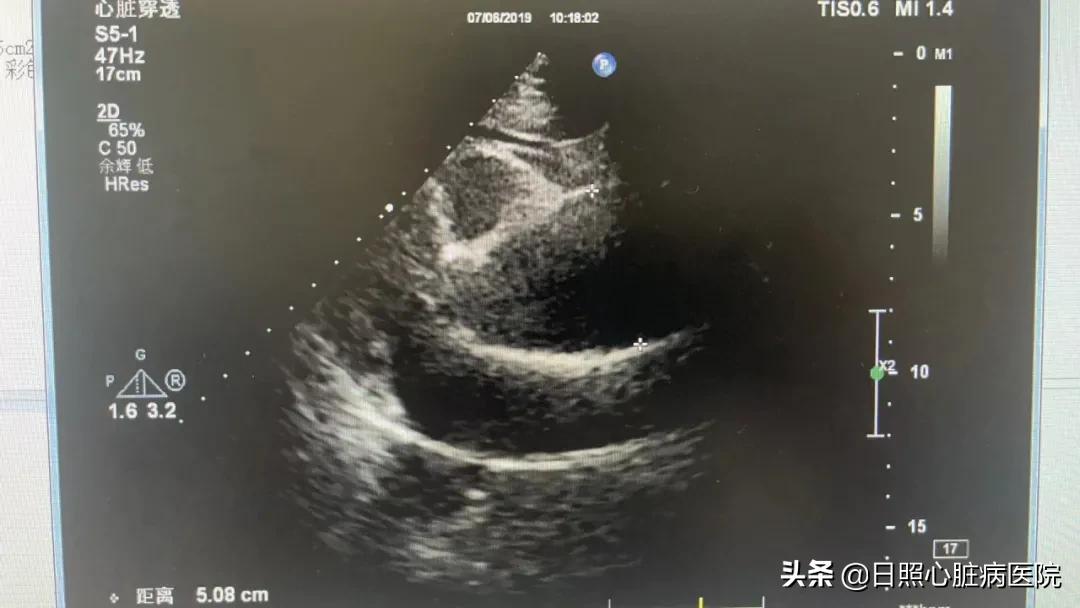

主动脉瘤在超声下表现为主动脉异常扩张,主动脉瘤可以有多种形状,动脉瘤近端颈部后壁,因主动脉延长而发生明显的扭曲,可能会认为是粥样硬化引起的狭窄;如果动脉瘤向前方扭转,会难以显示肾动脉水平,腹主动脉瘤近端也可能发生扭曲,呈“天鹅颈”样表现。瘤内腹壁血栓因为形成的时间和机化程度不同。表现为回声各异的同心层状结构,有时血栓可能发生局部的液化,表现为血栓内的低回声区,这可能会与夹层的表现相混淆,但是液化区和管腔之间通常被较厚的血栓分隔开。主动脉夹层可因血流漏入管壁内,被误以为附壁血栓而无法被发现。炎性动脉瘤在二维声像图上表现为主动脉周围分界不清的纤维化低回声区。

与诊断主动脉夹层一样,超声心动图是诊断主动脉瘤的主要影像学手段 。由于多数主动脉瘤无明显临床症状,故不易被发现。近年来,超声心动图以其简便、无创、可重复检查等优势应用于常规体检中,使得主动脉瘤的检出率较过去明显提高。